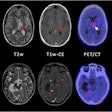

PET proves effective for guiding treatment of brain cancer

January 25, 2023